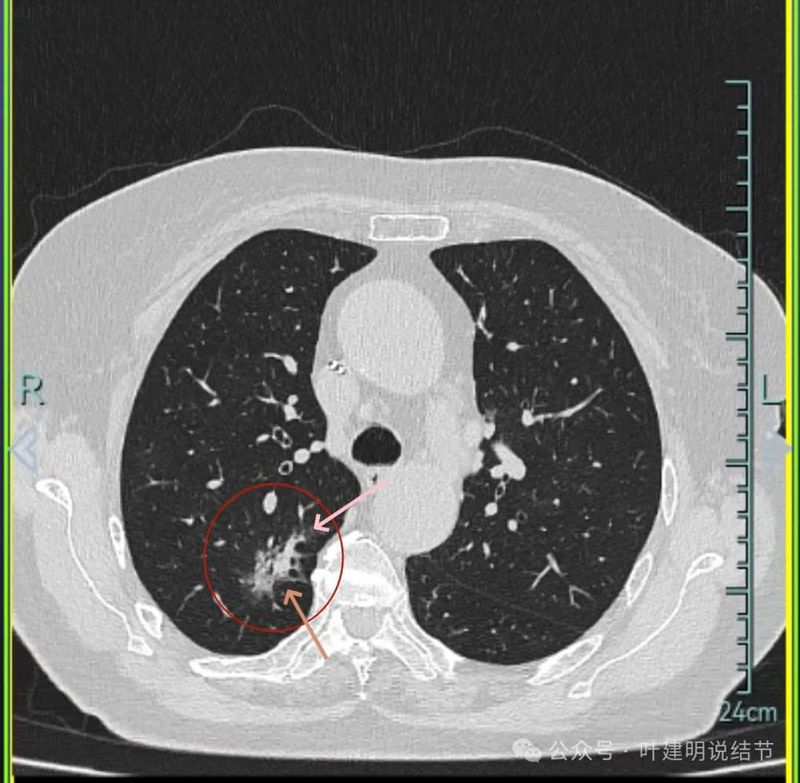

主病灶连续层面展示分析:

病灶出现,磨玻璃密度,轮廓与边界均清楚,灶内密度稍不均。

有明显血管进入,表面分叶,边缘不平,整体轮廓清。

边缘毛刺、表面不平、灶内偏实性成分、分叶明显,整体轮廓与瘤肺边界较为清楚。

灶内细支气管扩张、边缘毛刺较为锐利、有明显磨玻璃成分,磨玻璃成分的瘤肺边界清楚,病灶分叶明显。

灶内密度杂乱不均,内有小空泡征,表面不平。

灶内血管增粗穿行、磨玻璃成分明显,轮廓较清。

血管进入,磨玻璃成分,支气管扩张,边缘不平。

典型混合密度病灶,中间部分密度高偏实性,外围部分磨玻璃密度,两者之间交错存在,说明偏实性部分有侵袭性。磨玻璃成分与正常肺组织之间界限清楚,表面分叶,部分边缘毛刺,整体轮廓清。是非常符合恶性的影像表现。

灶内磨玻璃成分明显,并有异常增粗血管僵硬穿行于病灶内,支气管有扩张通气征,瘤肺边界清楚,实性成分明显。